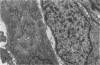

Charles River-CD Sprague-Dawley rats in 3 equal groups of 100 males and 100 females each were exposed to 12, 1, and 0 ppm of phenylglycidyl ether vapor for 24 months. Nasal tumors were first detected after 621 days' exposure at 12 ppm with an incidence of 11% in males and 4.4% in females. No nasal tumors were found at 1 ppm in rats exposed for 24 months. The nasal tumors, mostly epidermoid carcinomas, were derived from the respiratory epithelium and nasal glands, both of which revealed squamous metaplasia or dysplasia in the anterior nasal cavity. Most nasal tumors were confined to the anterior nasal cavity and occasionally invaded the dorsonasal bones and posterior nasal cavity. The undifferentiated glandular cells appear to differentiate to neoplastic squamous cells, because the ultrastructure of epidermoid carcinoma revealed traits of glandular cell differentiation in the neoplastic squamous cells. The features of glandular cell differentiation in the neoplastic squamous cells were intercellular or intracellular glandular lumens, secretory vesicles, mucus droplets, and intermediate cells showing both glandular and squamous differentiation. Squamous cells in the well-differentiated epidermoid carcinomas revealed abundant tonofibrils, desmosomes, glycogen particulates, and interdigitated cytoplasmic processes. These markers of squamous-cell differentiation were markedly reduced in the undifferentiated epidermoid carcinomas. The spindle-cell squamous carcinoma showed both squamous and fibroblastic-like differentiations. Some spindle cells had only fibroblastic-like differentiation, suggesting spindle-cell metaplasia of the squamous cells.